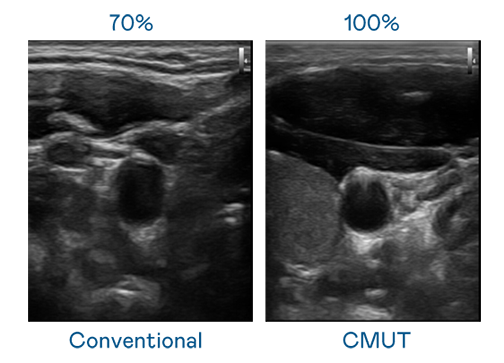

CMUT 技术是一种用电容式微机电元件来产生超音波讯号的技术。与传统 PZT 压电式技术相比,CMUT 频宽增加 30%,更宽频的超音波讯号让影像解析度大幅提升,是实现高影像品质医疗超音波扫描、促进精准医疗发展的关键技术。

超音波影像的解析度高低,首先取决于探头能发出的讯号频宽。麻花mv星空mv梦幻mv CMUT 可提供高清晰的超音波讯号,提供高频宽、高灵敏度、影像纹理细节更高的超音波影像,协助医护人员缩短影像判读时间及利用精准的医疗影像进行诊断。